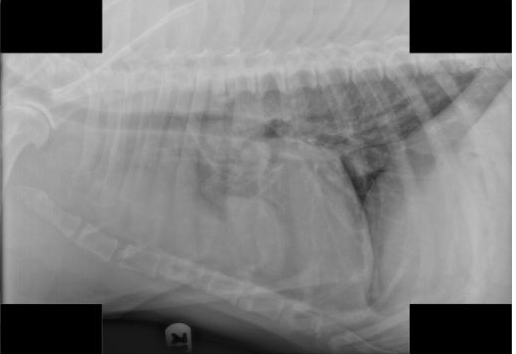

A 9-year old male Queensland Heeler presents with a four day history of progressive tetraparesis. Physical exam showed him to be weakly ambulatory with support. As part of your initial workup, you take chest X-rays which are shown below. Which of the following next steps is the most appropriate test to confirm your clinical suspicion about the cause of the dog’s signs?

The correct answer is a Tensilon (edrophonium) response test. Hopefully, you were able to identify the mass in the cranial mediastinum on the chest radiograph, as this was one of the keys to this case. This, in conjunction with the dog’s other signs, are suggestive that this dog has a thymoma and associated secondary myasthenia gravis. Tensilon (edrophonium) is a rapidly acting anticholinesterase that reverses signs of myasthenia within minutes in most dogs.

A chest CT would be a valid test to confirm the presence of the mediastinal mass and might be an appropriate test before surgery but would not bring you closer to a diagnosis if you already have identified the mass. An MRI of the brain would assess a CNS cause of the dog’s signs, which are unlikely, given the other findings. Similarly, a myelogram would assess if a spinal cord lesion caused the dog’s signs, but the rest of the findings in this case should point you in a different direction.